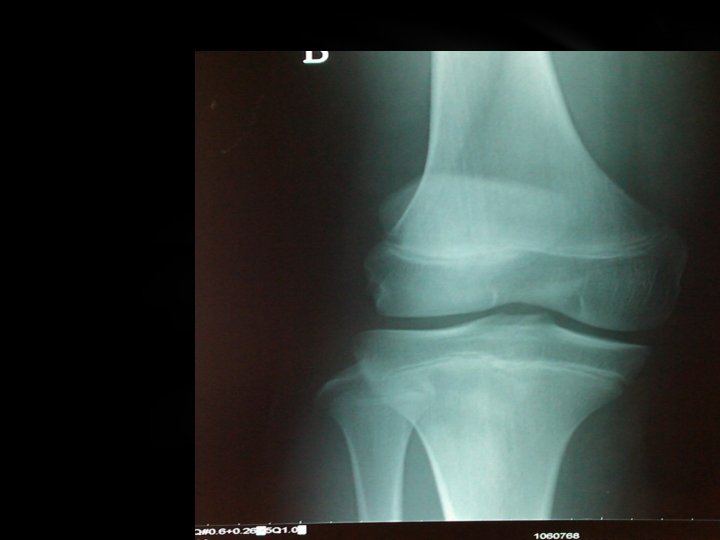

Exploración de rodilla dcha: Dolor en cara anterior con deformidad e impotencia funcional Pruebas complementarias: Rx rodilla dcha Arrancamiento tuberosidad tibial anterior

FRACTURAS FISIARIAS DE LA TIBIA PROXIMAL CLASIFICACIÓN IMPLICACIONES MECANISMO DE LESIÓN I. HIPEREXTENSIÓN RIESGO DE TRASTORNO VASCULAR II. VARO/VALGO HABITUALMENTE A CONSECUENCIA DE UN SALTO, PRÓXIMO A LA MADUREZ III. FLEXIÓN POSIBLE COMPRESIÓN DE LA PATA DE GANSO O EL PERIOSTIO TIPO DE SALTER-HARRIS I 50% NO DESPLAZADA II 30% NO DESPLAZADA III POSIBLE LESIÓN DEL LIGAMENTO COLATERAL ASOCIADA IV RARA V SE HA DESCRITO; HABITUALMENTE DIAGNÓSTICO TARDÍO

AVULSIÓN TRAUMÁTICA AGUDA DE LA TUBEROSIDAD TIBIAL • Lesión aguda (con frecuencia en la práctica deportiva) • Dolor y tumefacción importante e inmediata • Con frecuencia imposibilidad para mantenerse en pie o caminar • Con frecuencia reducción abierta y fijación interna • Rápida consolidación y retorno a las actividades completas